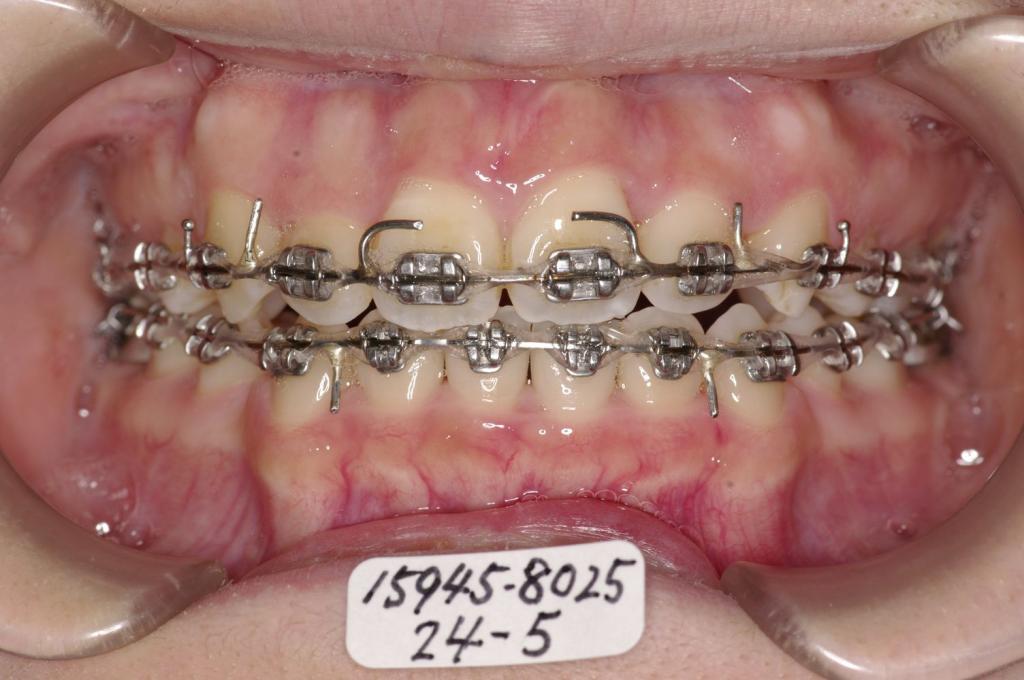

装置の種類及び治療法 診断:上下顎前突 叢生

治療方法および装置:マルチブラケット装置

High pull J-hook headgear

抜歯:右上64 /左上4

右下84 /左下48

装置写真

治療前

前歯、出っ歯・開咬の矯正治療前口内写真NO.1094